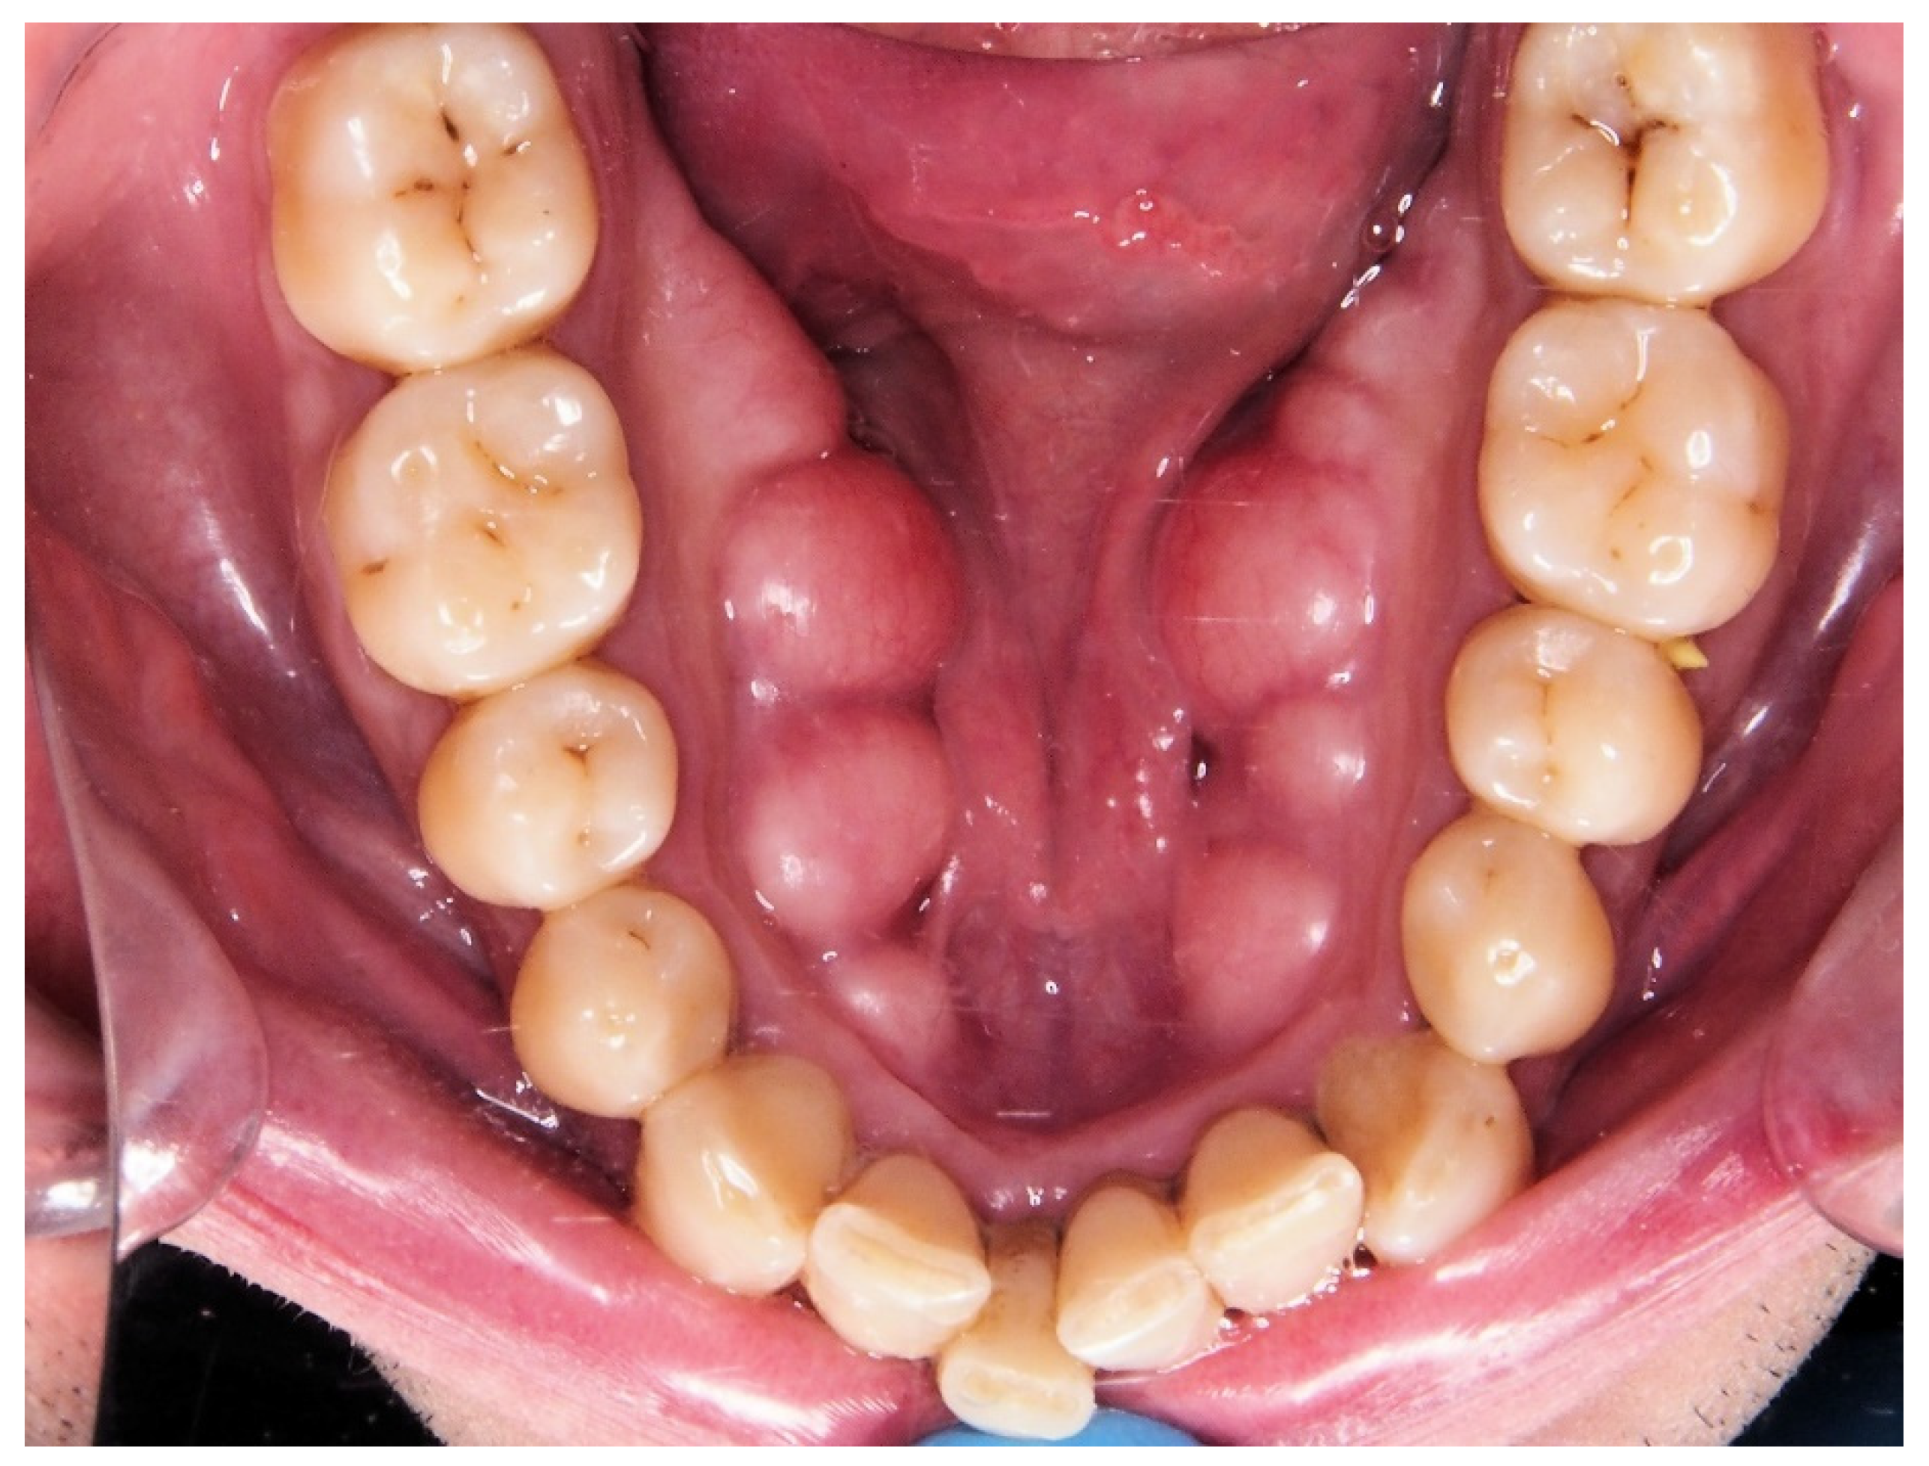

| 16. PNSP | PNS to P (see Figure 1). Length of the soft palate. |